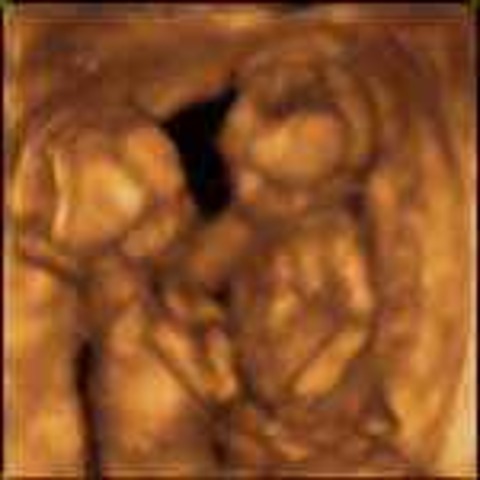

1.the fertilized egg is now called a blastocyst

2.It can reproduce itself through twinning at any time up to about 14 days after conception

• week5